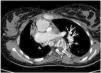

A 16-year-old female presented with a history of complex congenital heart disease requiring a right systemic-pulmonary fistula, with a bidirectional cavopulmonary anastomosis (Glenn procedure) at 6 years of age. She was admitted to the Pediatric Intensive Care Unit due to breathing difficulty and severe hypoxemia. With the suspicion of pulmonary thromboembolism, heparin sodium was started, and a new CT angiographic study was performed 24 hours later due to progressive clinical worsening. A thrombus was identified at the communication between the left superior vena cava and the left pulmonary artery, compatible with massive thromboembolism of the left lung (Fig. 1, see arrows). Treatment was started with recombinant tissue plasminogen activator (rTPA) in the form of an initial 30 mg bolus (0.5 mg/kg) followed by the perfusion of 0.04 mg/kg/h. After 36 hours, repeat control CT angiography evidenced important thrombus reduction with marked re-permeation (Fig. 2, see arrows).